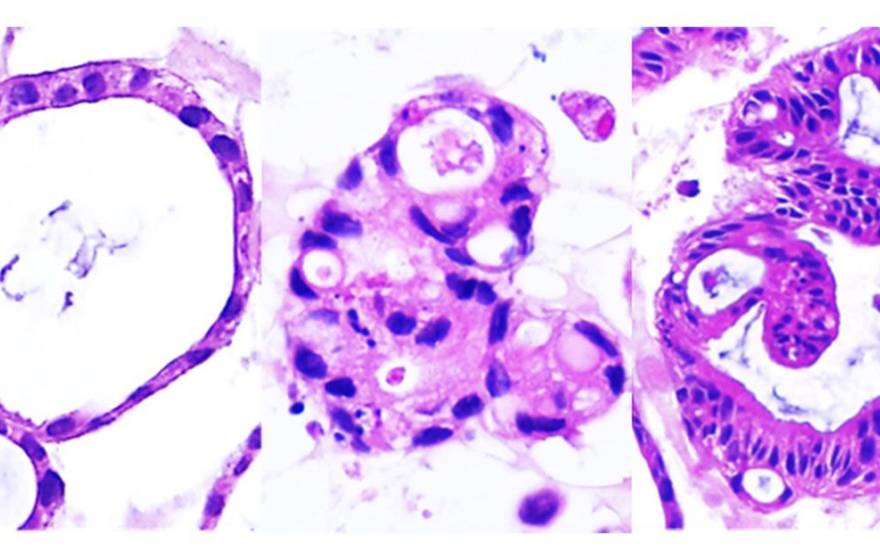

Organoids derived from gut stem cells reveal two distinct molecular subtypes of Crohn’s disease

UC San Diego researchers discover two distinct molecular subtypes of Crohn’s disease using patient-derived organoids, opening the door to personalized treatment for the chronic inflammatory bowel disease.